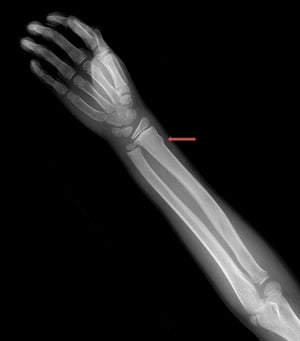

Frattura a legno verde del radio distale

Questa radiografia mostra una frattura a legno verde del radio distale, visibile come discontinuità nella parte radiale della corticale (freccia).

Questa radiografia mostra una frattura a legno verde del radio distale, visibile come discontinuità nella parte radial

ZEPHYR/SCIENCE PHOTO LIBRARY